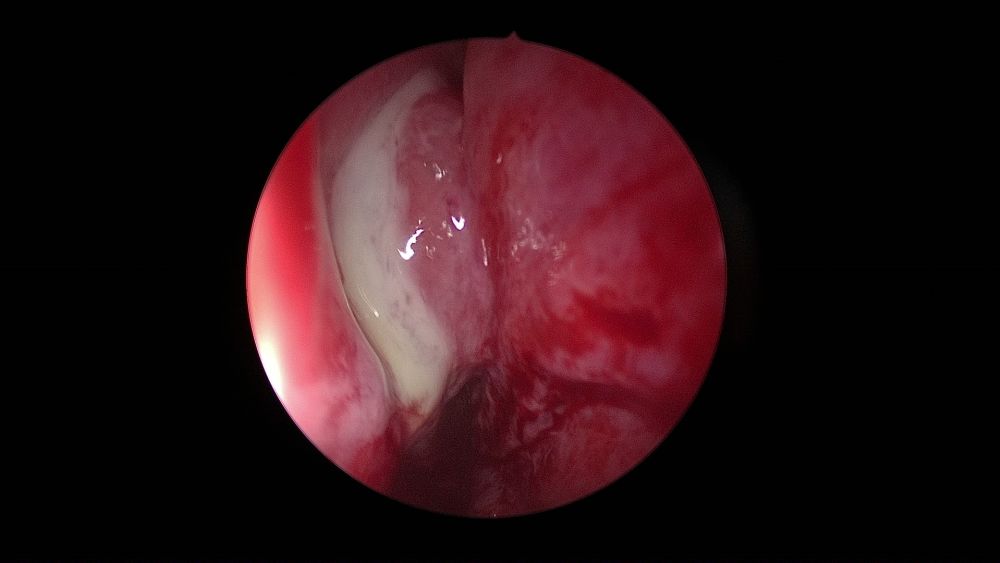

Varios estudios 14,16-17,31, coinciden en que la secreción purulenta nasal se identifica con mayor frecuencia en la SO en comparación con la rinosinusitis de otros orígenes, pero también se puede observar edema o pólipos. Algunos estudios han indicado que el 100% de los pacientes tenían hallazgos endoscópicos de infección 35.

El pus en el meato medio (66-8%), seguido del edema del meato medio (34-43%) y pólipos (12-34%) han sido los hallazgos endoscópicos más comúnmente informados en la SO en diferentes estudios26 (Figura 2).

Desafortunadamente, los hallazgos de la endoscopia nasal por sí solos, no son específicos, ya que otras patologías de los senos nasales pueden tener hallazgos infecciosos en la endoscopia, y algunos pacientes con SO pueden tener endoscopias nasales normales14.